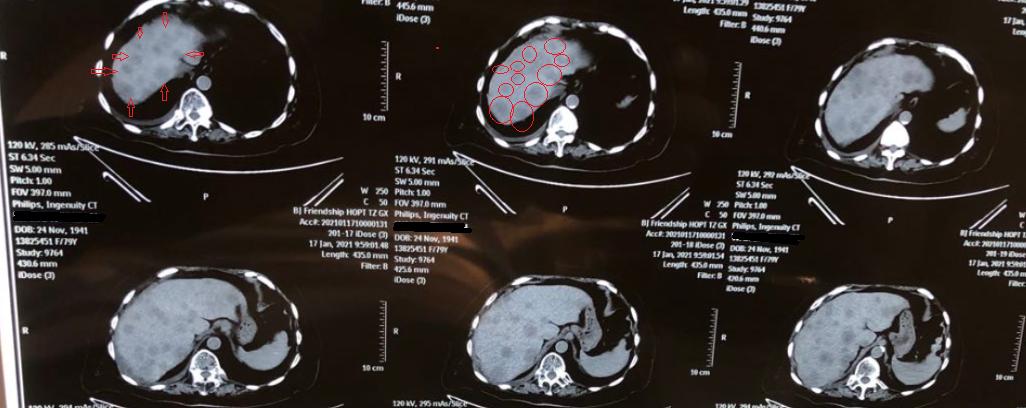

前日门诊又来了一位肿瘤肝转移的患者,把ct片子拿过来一看,心就沉了下去。原发灶其实问题不大,主要是肝转移太多,仅在ct的一个截面上,肉眼可见的转移灶就有十几个。

晚期发现非常容易,像文章开头讲的那位患者,不论是症状还是ct上的表现都十分明显。但是在早期,病灶较小的时候,诊断是比较困难的。

4、CT

CT是诊断肝转移肿瘤较为精确的检查方法,敏感性要高于超声,但是对于微小病灶有漏诊的可能。